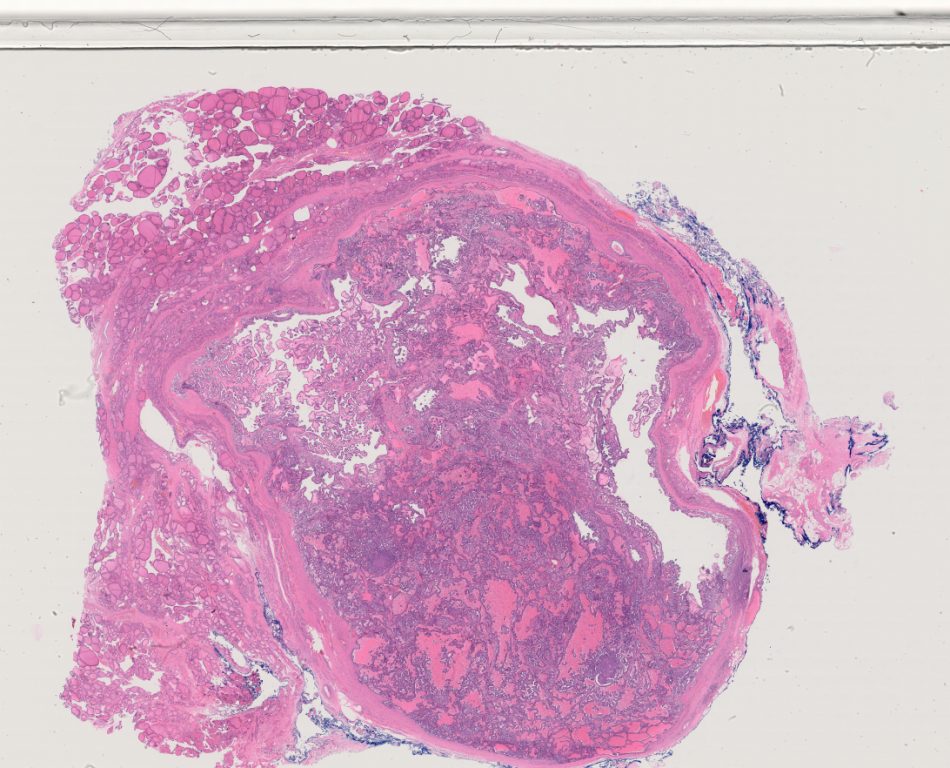

TSN 018.ndpi

139776

x

112896

40X